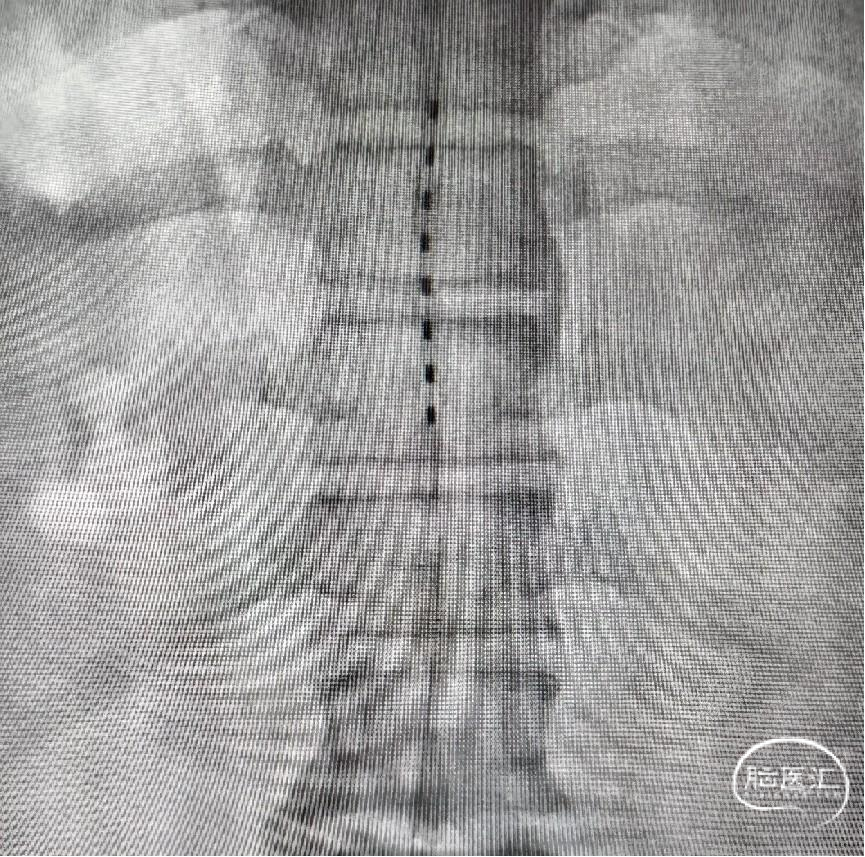

2024年8月8日在解放军总医院第七医学中心神经外科导管室局麻下行临时穿刺短时程电刺激植入术,手术过程顺利,术中测试中与患者反复沟通确认刺激后体验,确认刺激相关酥麻感覆盖腰部以下至足部全区域,将电极准确植入到目标节段。

图2. 电极触点主体覆盖T10、T11椎体节段。开启各触点刺激,刺激相关酥麻感覆盖腰部以下至足部的下肢全区域。